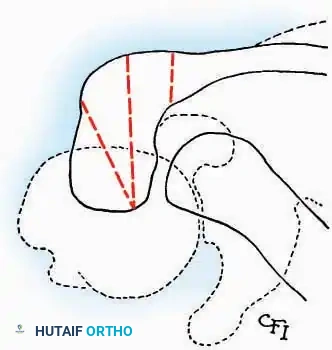

* Incision: Begin the incision on the lateral margin of the Achilles tendon near its insertion. Extend it distally to a point 4 cm inferior and 2.5 cm anterior to the lateral malleolus. (For trauma, a classic L-shaped extensile incision is often used, dropping straight down anterior to the Achilles, then curving gently toward the base of the 5th metatarsal).

* Incision: Incise the skin over the medial border of the Achilles tendon, starting 7.5 cm proximal to the calcaneal tuberosity. Extend it distally to the inferoposterior aspect of the tuberosity, curve it transversely around the posterior heel, and continue distally along the lateral surface of the foot to the tuberosity of the fifth metatarsal.